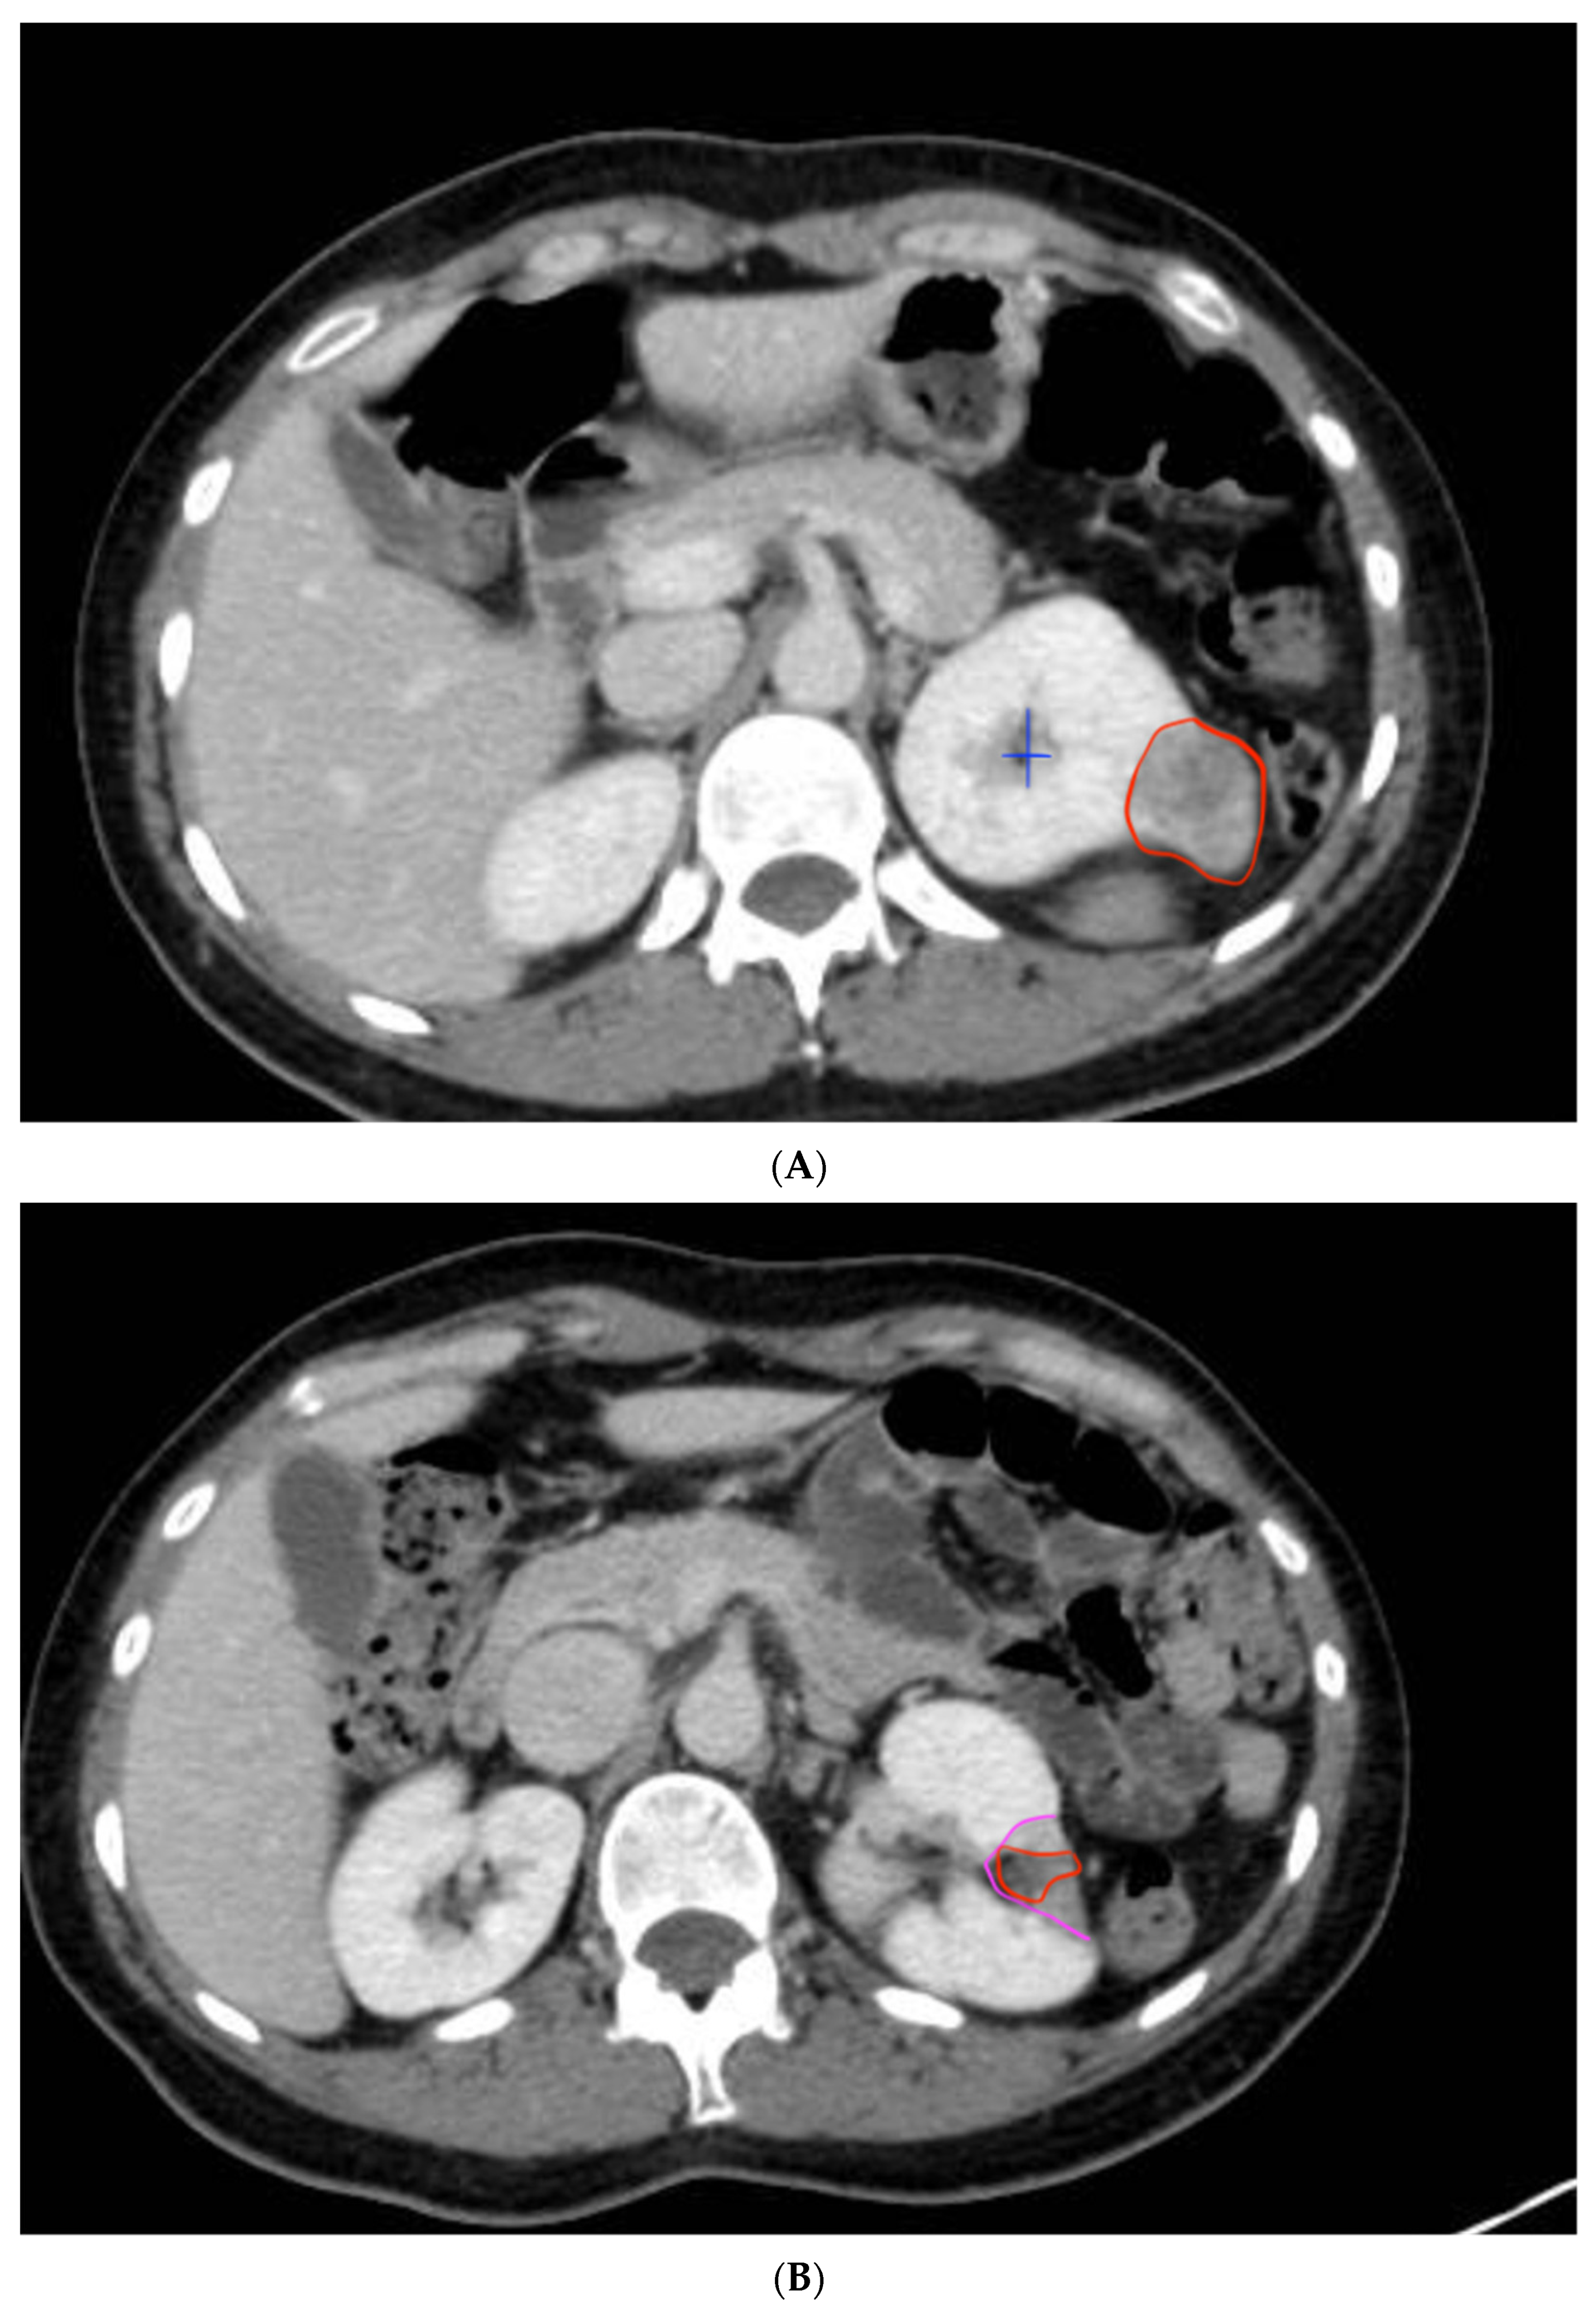

The persistent absence of contrast, hypervascularization, or vascular necrosis in the peri-tumoral area in the control CT was considered indicative of successful ablation, without recurrence (See Figure 6A,B).

Figure 6.

Kidney with exophytic tumor and control CT one year after surgery. (A) The first image shows a renal tumor on the posterior surface of the left kidney, measuring 3 cm, with characteristics of clear cell renal carcinoma (encircled in red). It is partially exophytic, located away from the renal hilum and the urinary collecting system. The blue cross marks the renal collecting system. (B) The second image shows the absence of the previously described mass. Post-operative changes are evident, with a scar in the area where the lesion was previously located and the morphological alterations of the kidney. Encircled in pink, the peritumoral necrotic halo is visible. In red, the bed where the tumor was located can be seen.